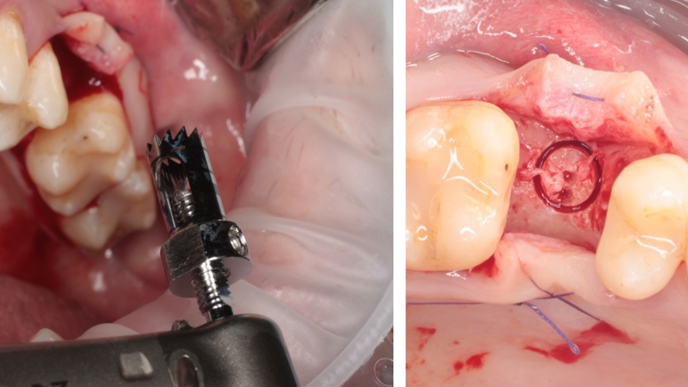

Clinical case: Ridge splitting technique using SmarThor + AnyRidge as expander

- Courtesy of Dr.Kwang-Bum Park, Korea -

AnyRidge, ridge splitting, GBR, Dr. Kwang-Bum Park, mandibular posterior, SmartThor, Mega-Oss, thin ridge, bone regeneration

AnyRidge implant system. SmarThor, Mega-Oss